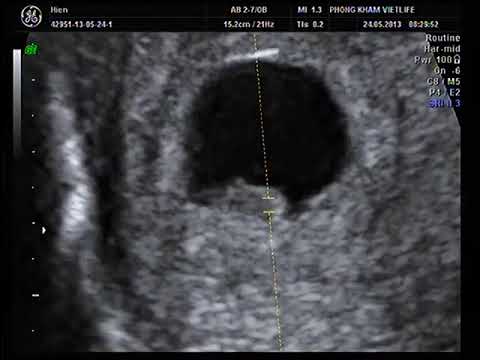

Về tim thai, tuần thứ 7 có thể nói là 1 tuần nhạy cảm khi nhắc tới vấn đề tim thai bởi đây là tuần đa số thai nhi đã có tim thai rồi. Vì vậy mẹ nào đi khám mà thấy con chưa có tim thai, thì rất lo lắng hoang mang. Tuy nhiên, cụ thể phải làm những gì thì khi các mẹ đi khám, chắc chắn bác sĩ sẽ tư vấn, và thông thường là phải làm xét nghiệm.

Có những trường hợp chưa thấy tim thai do yếu tố khách quan như tính sai tuổi thai hoặc thai nhi phát triển chậm. Nếu mẹ không có dấu hiệu đau bụng hay ra máu thì thường bác sĩ sẽ chỉ định chờ thêm vài ngày hoặc 1 tuần nữa rồi khám lại. Ở những trường hợp có nguy cơ, việc phải khám thai nhiều lần là điều cần thiết để có kết luận chính xác các mẹ nhé.

Thai nhi 7 tuần tuổi đã có những bước phát triển nhất định cả về hình dáng bên ngoài cũng như các chức năng bên trong của cơ thể. Chính vì thế, đây là giai đoạn thích hợp để mẹ bầu tiến hành siêu âm hình ảnh thai nhi và kiểm tra quá trình phát triển của bé yêu. Hình ảnh siêu âm thai 7 tuần tuổi sẽ cho biết nhiều chỉ số sức khỏe quan trọng giúp mẹ hình dung rõ ràng, cụ thể mức độ phát triển của bé yêu vào thời điểm này.